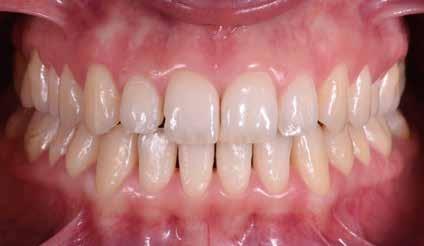

> La documentazione a dieci anni mostra la stabilità del caso e

come l’occlusione, elastodonticamente individuata, costituisca anche la contenzione stessa. La paziente ha smesso di

Considerazioni

indossare l’apparecchio elastodontico dopo due anni e mezzo di terapia, conservando parametri occlusali e posturali in rapporto corretto tra loro.

Nel 2019 si è provveduto all’avulsione chirurgica degli elementi dentari 18, 28, 38 e 48.

Alla risoluzione della malocclusione scheletrica e dentale si associa un netto recupero della postura con conseguente miglioramento della curva cervicale, come è possibile verificare nella teleradiografia finale.